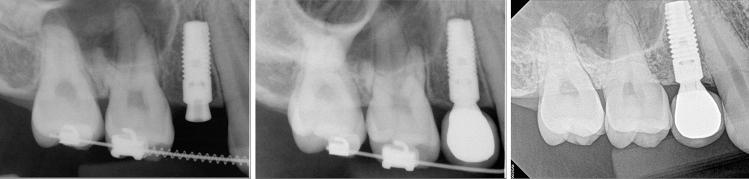

The purpose of the retrospective study was to investigate the long-term result of implant-induced injury on the adjacent tooth. The subjects of this retrospective study were patients who had received implants and had tooth injury; direct invasion of root (group I), root surface contact (group II), or < 1 mm distance of the implant from the root (group III). Clinical and pathological changes were periodically examined using radiographs and intra-oral examinations. Paired t-tests and chi-square tests were used to evaluate the implant stability quotient (ISQ) of implant and tooth complications, respectively (α = 0.05). A total of 32 implants and teeth in 28 patients were observed for average 122.7 (± 31.7, minimum 86) months. Seven teeth, three of which were subsequently extracted, needed root canal treatment. Finally, 90.6% of the injured teeth remained functional. Complications were significant and varied according to the group, with group I showing higher events than the others. The ISQs increased significantly. One implant in group I resulted in osseointegration failure. The implant survival rate was 96.9%. In conclusion, it was found even when a tooth is injured by an implant, immediate extraction is unnecessary, and the osseointegration of the invading implant is also predictable.

摘要

这项回顾性研究的目的是调查种植体对邻牙造成损伤的长期结果。该回顾性研究的对象是接受过种植体植入且存在牙齿损伤的患者;包括牙根直接受侵(I组)、牙根表面接触(II组)或种植体与牙根距离<1mm(III组)。通过X线片和口腔内检查定期观察临床和病理变化。分别采用配对t检验和卡方检验评估种植体的种植体稳定性商数(ISQ)和牙齿并发症(α=0.05)。共观察了28例患者的32颗种植体和牙齿,平均观察时间为122.7(±31.7,最短86)个月。7颗牙齿需要进行根管治疗,其中3颗随后被拔除。最后,90.6%的受伤牙齿仍保持功能。并发症明显且因组而异,I组的并发症发生率高于其他组。ISQ值显著增加。I组中有1颗种植体发生骨结合失败。种植体存活率为96.9%。总之,研究发现即使牙齿受到种植体损伤,也无需立即拔除,侵入性种植体的骨结合情况也是可预测的。